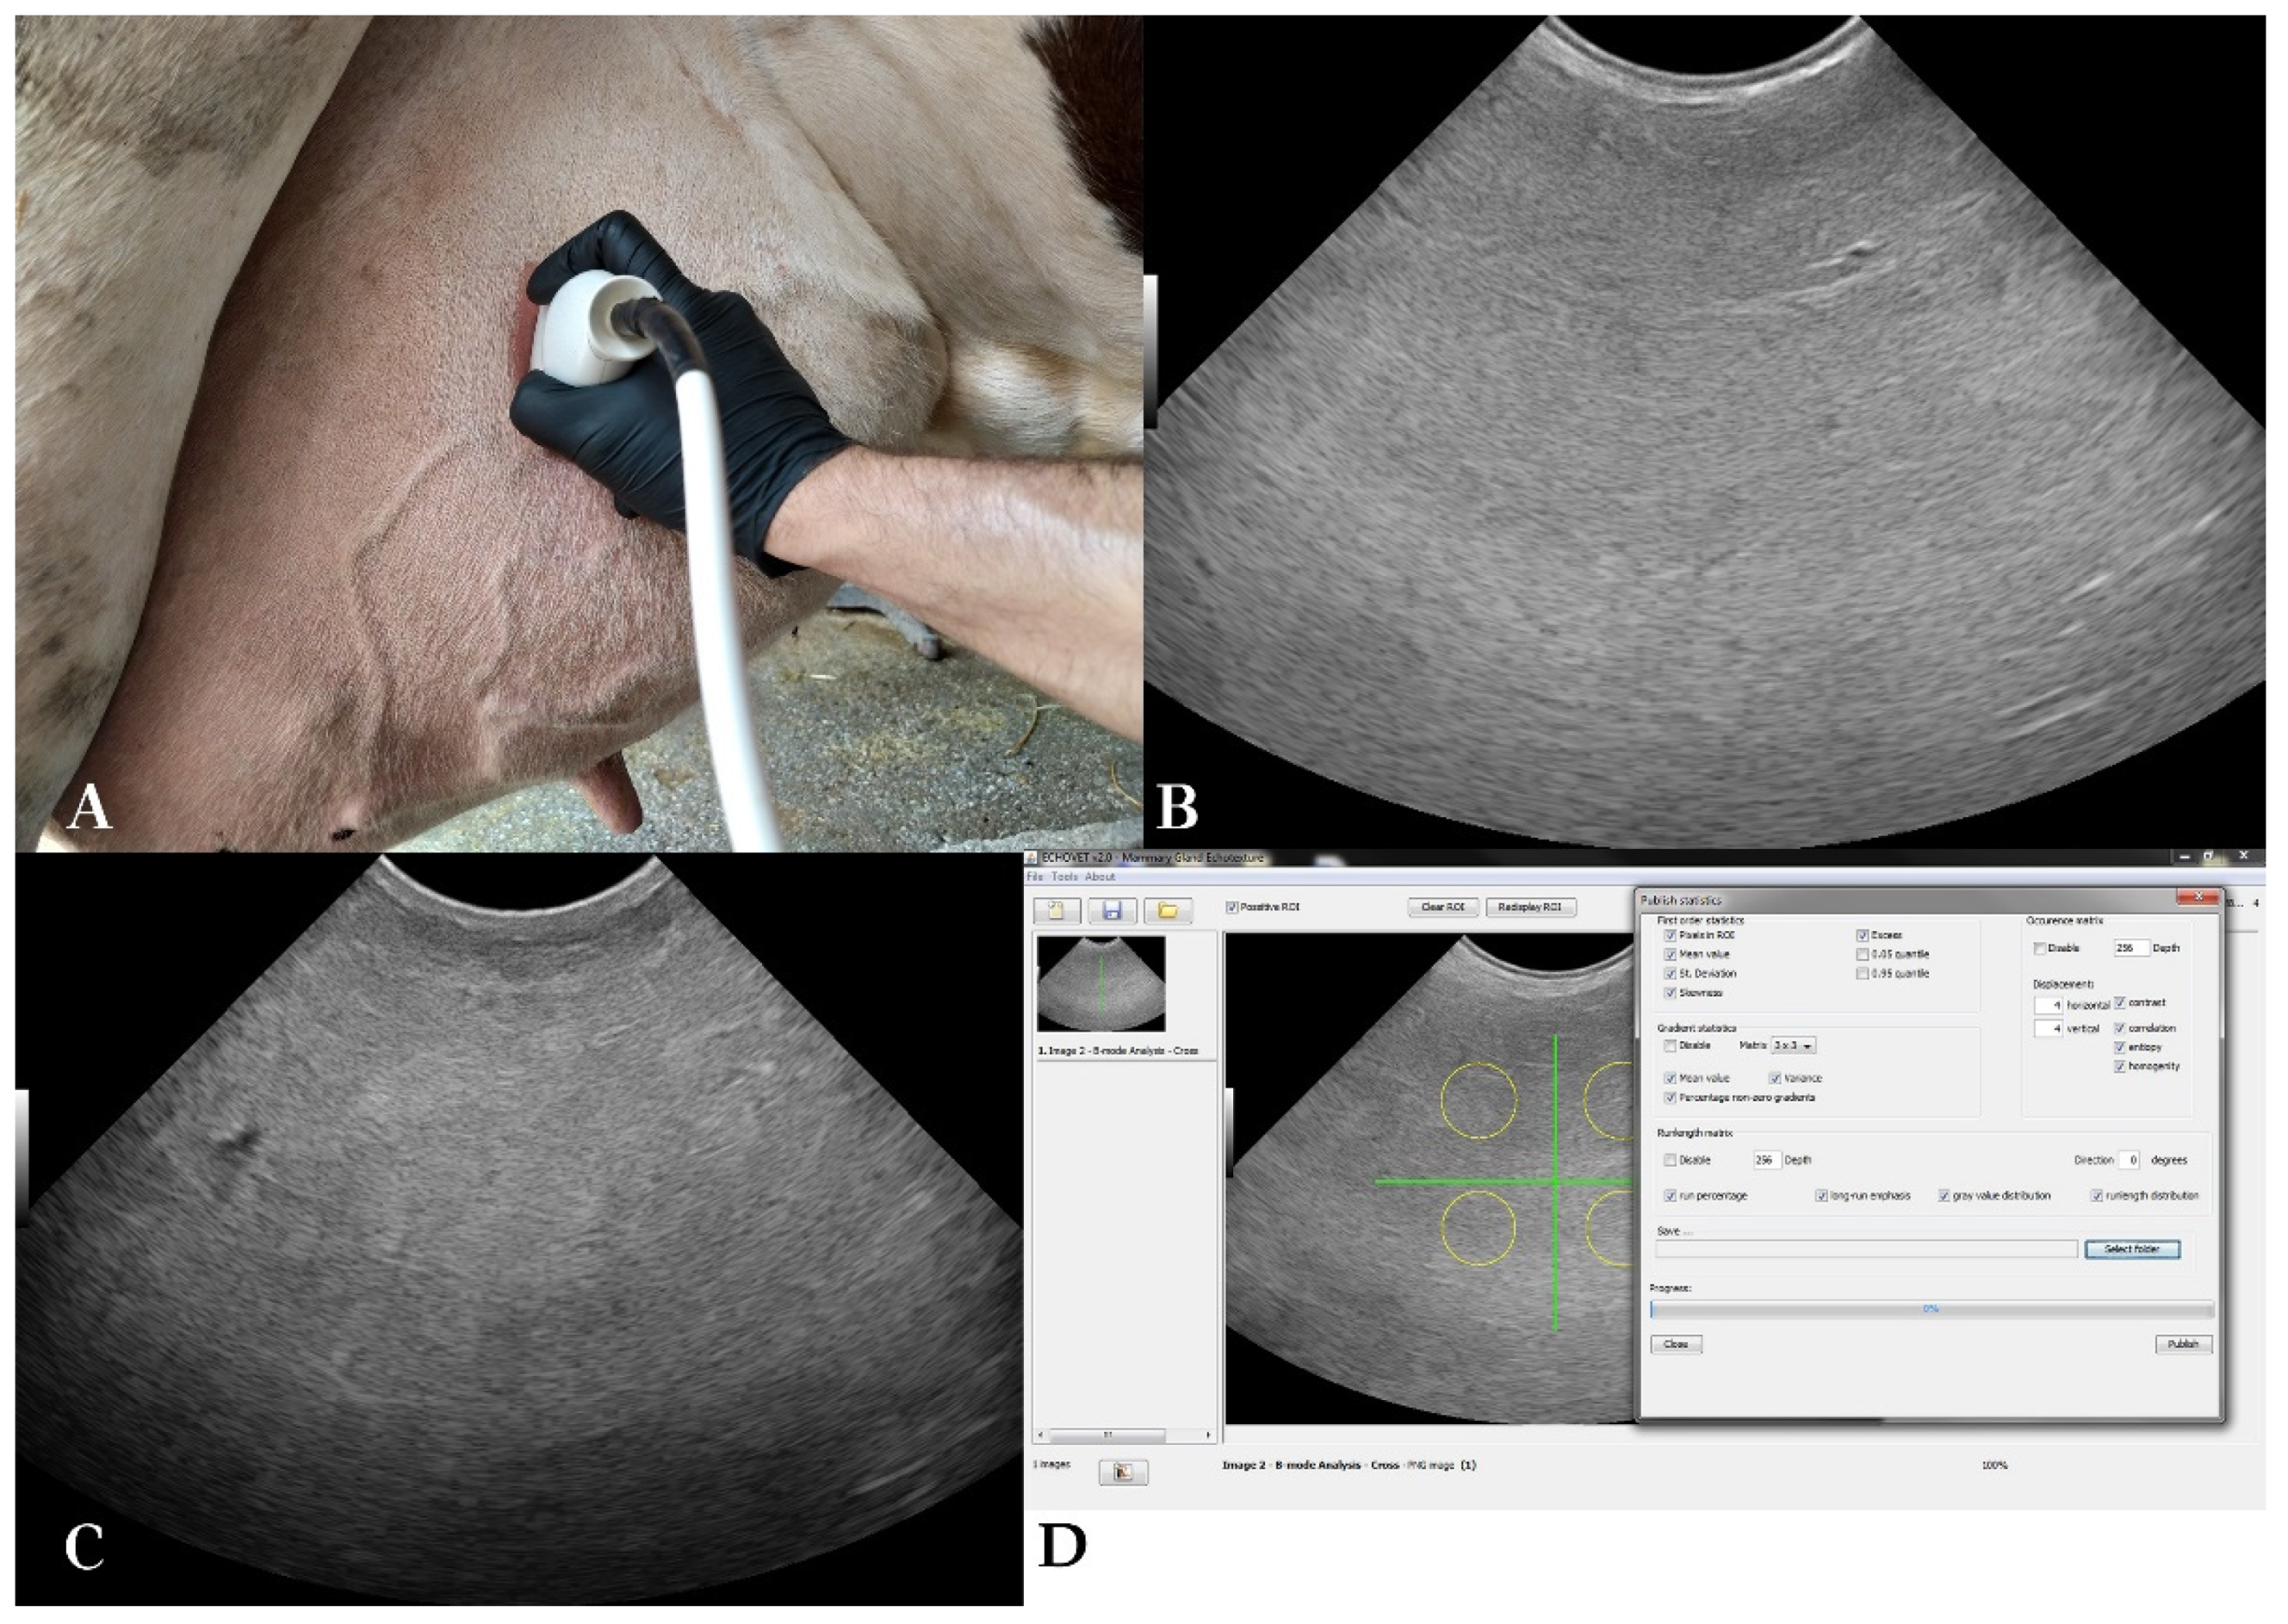

A straight part of the milk vein was selected for the measurement located at the midpoint between its cranial and caudal part. The area was shaved, washed, degreased with 70% alcohol and covered with coupling gel (Figure 1). To avoid compression of the vein while ensuring sufficient contact, an appropriate amount of coupling gel was applied on the transducer, without the latter directly touching the skin. First, the transducer was positioned in cross-section to the vein. Distance of the milk vein from skin surface (D1) (cm), its vertical diameter from intima to intima (D2) (cm) and vein area in cross-section (A) (cm2) were measured from B-mode images.

Then, the transducer was positioned longitudinally to the vein, and Color Doppler gate was activated and placed at the center of the milk vein. Blood flow sample volume cursor included at least 2/3rds of the vein diameter, 16-20 mm wide, and theta angle was 60o (Figure 1). Blood flow was examined for 2 minutes per vein and 5 optimal spectral Doppler images were obtained from each milk vein measurement for further processing with MyLab™_Desk v. 9.0 software (Esaote S.p.A., Genoa, Italy). Blood flow parameters used were time-averaged mean velocity (TAMV) (cm/s), peak velocity (Vpeak) (cm/s) and milk vein blood flow volume (BFVol) (L/min) [23]. The total number of spectral Doppler sonograms used was 690 [345 measurement days * 2 milk veins (right/left) per cow].

Udder parenchyma was examined with B-mode ultrasonography transcutaneously using a portable ultrasound scanner (MyLab™ OneVET, Esaote S.p.A., Genoa, Italy), equipped with a broad-bandwidth multi-frequency convex probe (SC3421, Esaote S.p.A., Genoa, Italy; 2.5–6.6 MHz). All four udder quarters were examined at each measurement day and two optimal B-mode images per quarter were acquired. The probe was placed in coronal plane to examine the front quarters and in sagittal plane for the rear quarters, 15–20 cm above the base of each teat (Figure 2). Ultrasound settings remained constant throughout the scans; frequency 6.6 MHz, scanning depth of 15 cm, gain 58% and time-gain compensation in neutral position.

The total number of sonograms used was 2,760 (345 measurements x 4 udder quarters x 2 B-mode images obtained from each udder quarter). The ultrasound scanner produced images with a resolution of 720 by 540 pixels. Each pixel had one of the possible shades of grey (0 to 255). Echotexture analysis procedure presented in Figure 2 was performed with EchoVet v.2.0 software (Aristotle University of Thessaloniki, Greece) [25]. Each image was divided into four imaginary quarters [30]. A circular region of approximately 5,000 pixels was manually selected within each of the image quarters. Selection criteria were physiological gland parenchyma, with medium homogeneous echogenicity, avoiding mammary vessels [3]. The overall region of interest selected from each B-mode image was 20,000 pixels [13].

Figure 1. Spectral Doppler examination of the blood flow in the milk vein. A. Measurement of the blood flow features of a dairy cow’s milk vein on the 14th day in lactation, B. Measurement of the blood flow features of a dairy cow’s milk vein on the 35th day in the dry period, C: Measurement of the distance from skin surface, diameter and cross-sectional area of the milk vein, D. Placement of the probe for Doppler measurement of blood flow.

Figure 2. B-mode udder ultrasonography and echotexture analysis: A. Ultrasonographic examination of the mammary parenchyma, B. B-mode sonogram of a cow’s right rear quarter on the 75th day in lactation, C. B-mode sonogram of a cow’s right rear quarter on the 7th day in the dry period, D: Echotexture analysis of a B-mode sonogram of the udder (EchoVet v.2.0).